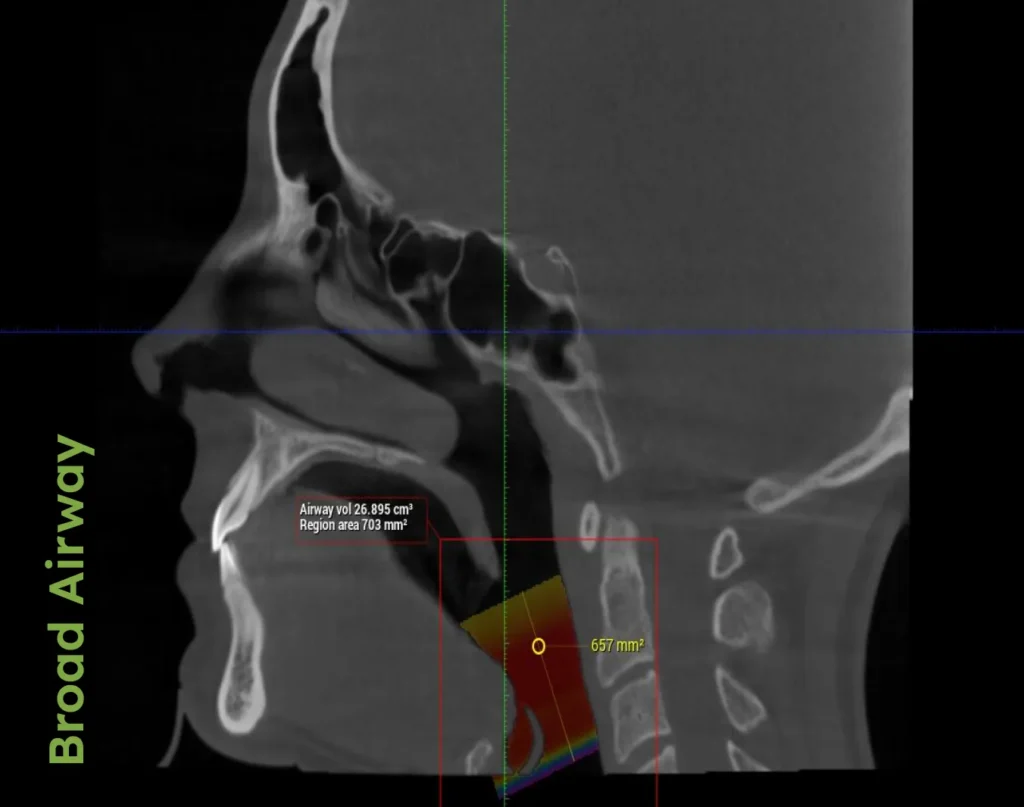

“We treat TMJD by addressing the primary culprit: a compromised airway. Our holistic approach integrates how the muscles, bite, posture, and respiratory conditions impact the jaw, creating personalized plans for a pain-free, healthier life,” explains Dr. Porter. He further emphasizes the necessity of understanding the interconnected nature of body systems, advocating for a treatment approach that considers overall physiological health to ensure the effectiveness of TMJD treatments.

Dr. Porter discusses in his book AIM the critical relationship between TMJD and airway health. A compromised airway can lead to dysfunctional jaw positioning, which stresses the temporomandibular joint and related muscles. This section details how enhanced airway health can alleviate TMJD symptoms, providing relief and preventing further complications.